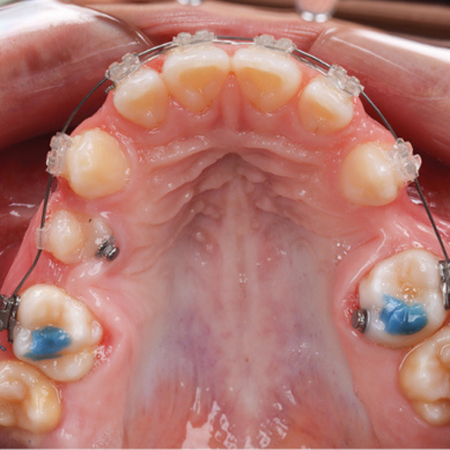

Invisalign Palatal Expander: uma nova opção para expansão rápida da maxila em pacientes em crescimento

INTRODUÇÃO: O Invisalign Palatal Expander (IPE) é uma inovação recente desenvolvida pela Align Technology, lançado no Brasil em 2025, com o objetivo de promover a expansão rápida da maxila em pacientes em crescimento. OBJETIVO: Este artigo apresenta um caso clínico de um paciente com 7 anos de idade, mordida cruzada posterior unilateral, tratado com o uso do IPE, destacando a evolução clínica e os resultados obtidos. RELATO DO CASO: Foram utilizados 40 expansores, totalizando 10...

Invisalign Palatal Expander: a new option for rapid maxillary expansion in growing patients

INTRODUCTION: The Invisalign Palatal Expander (IPE) is a recent innovation developed by Align Technology, launched in Brazil in 2025, designed to achieve rapid maxillary expansion in growing patients. OBJECTIVE: This article presents a clinical case involving a 7-yearold patient with a unilateral posterior crossbite treated using the IPE, highlighting the clinical progression and treatment outcomes. CASE REPORT: A total of 40 expanders were used, providing 10 mm of expansion over 30...